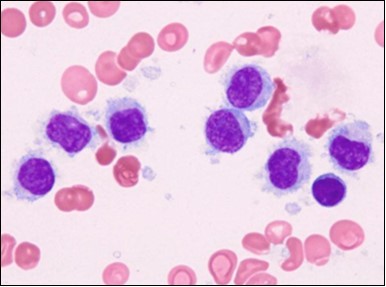

The classic hairy cell is medium sized with a magnitude of 10-14µm. The moderately abundant or variable cytoplasm may be transparent or mildly basophilic. The cellular surface with the characteristic serrated perimeter depicts innumerable fragile or stout extensions of cytoplasm ,particularly discernible on the phase contrast and electron microscopy. The cytoplasm may exhibit vacuoles with occasional azurophilic granules4. The nucleus may be elliptical or reniform, folded or indented with a coarse, reticulated or a finely dispersed chromatin and inconspicuous nucleoli along with infrequent mitosis. Bone marrow aspiration or bone marrow trephine biopsy may be inadequate for diagnosis in 30%-50% individuals4. The trephine sections of the bone marrow may depict a characteristic interstitial pattern of leukaemic infiltration. Generally the bone marrow is hyper-cellular, though it may be hypo-cellular in 10-15% individuals4. The leukaemia cell ingress may be diffuse or partial, although diffuse infiltration is frequent. The partial variety of leukaemic dissemination may be ineptly categorized with an indeterminate differentiation from the uninvolved marrow. The malignant insertions may initially emerge as miniature, undefined, cellular loci. The formalin fixed, paraffin embedded sections may elucidate a crystalline zone or a “halo” appearance of the cells with a circumscribed nucleus on account of the plentiful cytoplasm4. The cellular margins may be intertwined. Fixation of bone marrow smears with Zenker’s fixative may demonstrate a retracted cytoplasm of the hairy cells with a consequent disconnected structure. The bone marrow in the absence of a malignant process may be hypo-cellular or hyper-cellular. Reticulin stains may delineate an enhanced accrual of broad, dense reticulum fibres surrounding the aggregates of leukaemia cells with the fibrous circumlocution of individual malignant cell and fibrotic extensions into the abutting, uninvolved bone marrow4.

The leukaemia cells may enunciate a characteristic immune phenotype, crucial for a confirmatory diagnosis. The peripheral blood mononuclear B cell population may display a kappa or lambda light chain restriction. The phenotype of classic hairy cell leukaemia may be delineated by concurrent, immune reactive CD19+ CD20+,CD 11c+, CD25+, CD103+ and CD123+. An intensely immune reactive CD200+ and a non reactive CD27- antigen may be present2, 4. Evaluation of a trephine bone marrow biopsy and bone marrow aspirate may define the degree of tumour infiltration. A dry tap on account of prominent bone marrow fibrosis may be elucidated at preliminary diagnosis. A decline in the normal haematopoiesis may account for a hypo-cellular marrow in 10% instances. Gradation of cellular infiltrating of the leukaemia within the bone marrow may be appropriately investigated with immune –histochemical stains2, 4. Immune staining for CD20+, annexin 1 and VE1 (a BRAF V600E stain] may validate the diagnosis and precisely analyse the extent of malignant bone marrow infiltration[8]. Determination of BRAF V600E mutation may be critical in therapeutically non responsive individuals with applicable standard therapy or in instances of multitudinous reoccurrences[9]. Deploying inhibitors of BRAF V600E gene may be efficacious in patients impervious to approved therapy. The mutation necessitates a comprehensive scrutiny of the implicated individuals with a sensitive molecular assay which may discern up to < 10% of the hairy leukaemia cells appearing in the peripheral blood smears or bone marrow aspirates diluted with peripheral blood or aspirates elucidating a dry tap[2,4]. Allele specific polymerase chain reaction (PCR) or a next generation sequencing may be optimally employed to circumvent false negative outcomes. If the leukaemia cells are sparse or if particularly sensitive & efficacious molecular techniques are not accessible, the application of appropriate immune histochemical stains to the bone marrow biopsy such as a BRAF V600E mutation stain (VE1) may detect the hairy cells and conclusively diagnose the condition[2,4,10]. Figure 1, Figure 2, Figure 3, Figure 4, Figure 5, Figure 6, Figure 7, Figure 8, Figure 9, Figure 10, Figure 11, Figure 12, Figure 13, Figure 14.

Figure 7.HCL: blebs on the cellular surface with fine nuclear chromatin(23).

Figure 10.HCL: inconspicuous nucleoli, open-ended chromatic and surface protrusions(26).